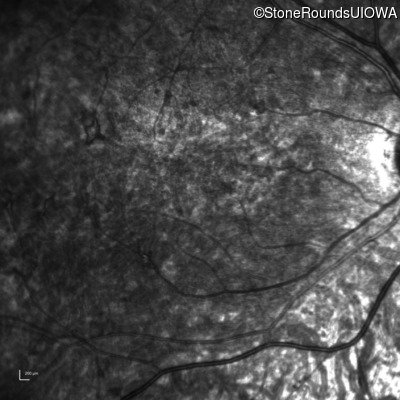

Age at visit: 10 years

Age at visit: 11 years